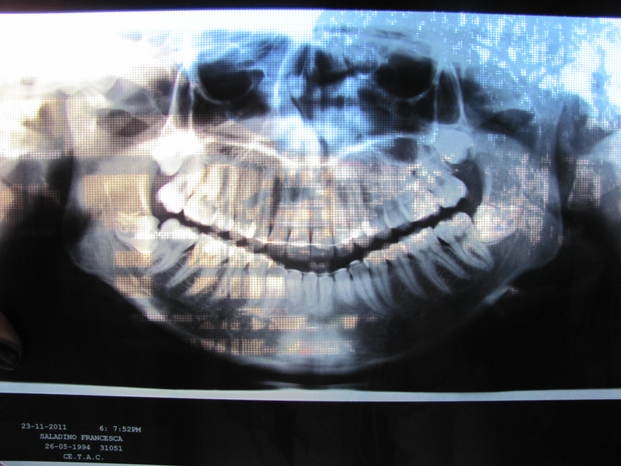

La radiografia dei miei denti. Per farla vedere bene l'ho messa sulla finestra, ma si vede l'alberello dietro XDD

Come vedete è così da tutti e due i lati. E sopra non sono messa meglio.